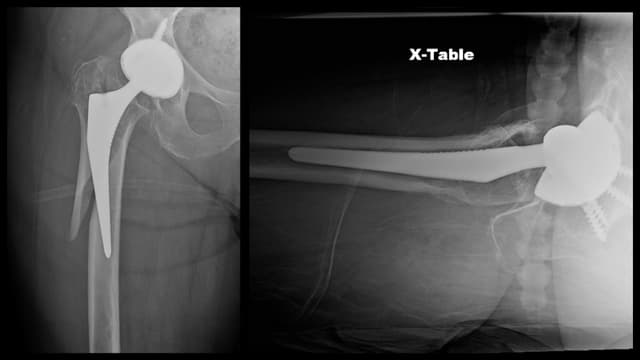

Post-op